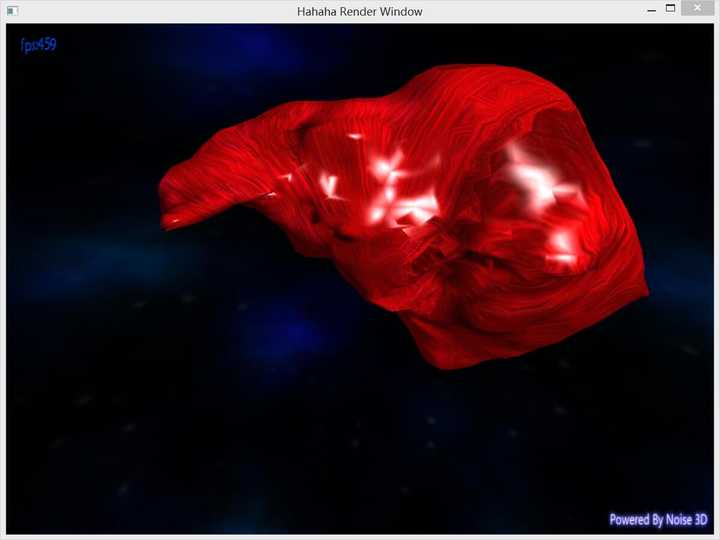

所以最后折衷一下做个网格简化吧!

好多了好多了!